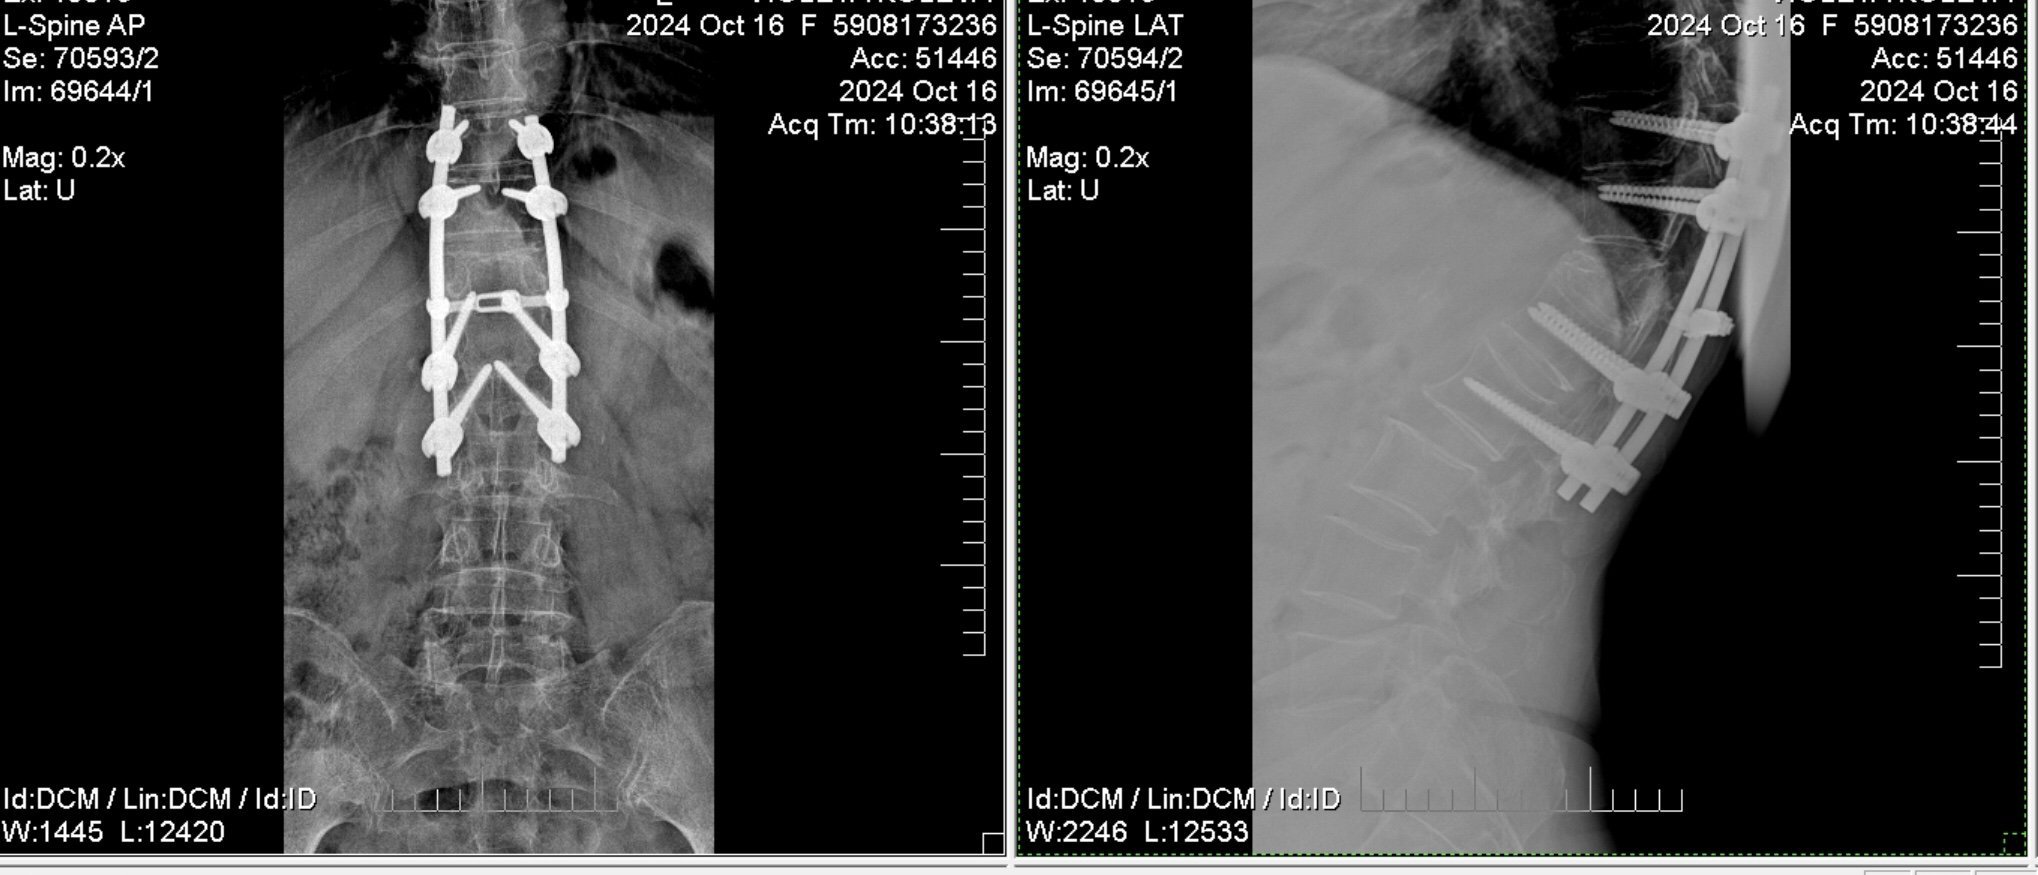

Здравейте г-н Георгиев, бих искала консултация относно състоянието на майка ми. Оперирана е 2021 заради фрактура на прешлен на три места и е поставен гръбначен стабилизатор, има няколко остеопорозни прешлени, почти всички вторични болки от зарастването на импланта в процеса на възстановяване са изчезнали или в много редки случай има леко сковаване след силна физическа преумора. Лятото мисля че юли месец 2024г. при спъване майка ми имаше лек инцидент и леко падане, но не на гърба, а се е подпряла на лакът и колена, никакви сериозни симптоми и болки не последваха, но след месец два след малко по-голямо физическо натоварване в градината на вилата се появиха отделни стрелкащи болки и леко сковаване в ляво от долната страна на импланта при ставане от леглото след продължително лежане , също по-рязко ставане от седнало положение или вдигане на ръцете нагоре и изпъване. Болките са моментни не постоянни, но се притеснявам, с оглед на прекараната операция да не би да има някаква травма, на която трябва да се обърне внимание. Направихме снимка октомври 2024 и по снимката по долу и разчитането й не бяха описани никакви травми на гръбнака или импланта, но стрелящата болка се появява от време на време за ден или няколко после изчезва и след време пак се появява, в момента е вече трети ден, сякаш малко поотшумява от топли нагрявки, но е упорито и болезнено. Би могло да е нараняване на мускул, сухожилие или настинка, но няма  конкретно предаване и изтръпване на крайници, няма слабост в гръбначния стълб, няма и болка при продължителни разходки, тя се разхожда по 5-6 км на ден, нито при продължително стоене права. Само придръпването и срелкащата болка, която минава до 5-6 мин след ставане. Бихте ли погледнали снимката за мнение, да не би лекарите да пропускат нещо, мислим също да направим до дни ЯМР за всеки случай, благодаря предварително!

От направените рентгенови снимки няма данни за проблем с импланта. Меките тъкани не могат да се оценят от тази снимка. Макар да са преходни болките, не Ви съветвам при тази операция да има претоварвания.